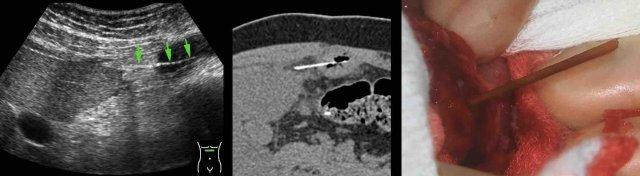

Bệnh nhân nam 33 tuổi này (có tiền sử cắt đoạn ruột lúc 4 tuổi) nhập viện với đau thượng vị và CRP 155. Siêu âm và CT xác nhận cấu trúc dạng xương (mũi tên) xuyên thủng quai ruột non có dính.

Qua đường mổ nhỏ (mini-laparotomy), một mảnh xương sắc dài 6 cm đã được lấy ra. Bệnh nhân đã ăn vịt Bắc Kinh hai ngày trước đó.

Bệnh nhân nam 83 tuổi còn khỏe mạnh nhập viện với đau bụng trên cấp tính và CRP 90. CT phát hiện cấu trúc dạng xương mắc kẹt trong hỗng tràng. Sau 24 giờ điều trị bảo tồn bằng kháng sinh, cơn đau không giảm và CRP tăng lên 230.

Trong phẫu thuật, một mảnh xương sắc nhọn gây thủng đã được lấy ra dễ dàng qua một đường rạch nhỏ trên hỗng tràng, không cần cắt đoạn ruột.

Bệnh nhân hồi phục nhanh chóng và hiện tại, mười một năm sau, ở tuổi 94, ông vẫn trong tình trạng sức khỏe hoàn hảo. Ông vẫn không thể tin rằng mình đã từng nuốt phải một mảnh xương lớn như vậy.